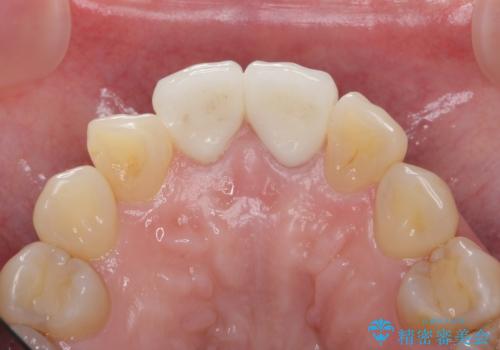

結果、気になっていた色と角度が良くなり、大変喜んでいただけました。

- 48.4万円 内訳:ジルコニアクラウンスペシャル 13万円x2、ファイバーコア 2万円x2、仮歯 1万円x2、精密根管治療(イニシャル) 6万円x2 (税別)費用は治療当時の料金となります

右上1はひっこめた量が大きかったため、反対側の1番と切端をそろえるのに、多少長さは長くなりました。